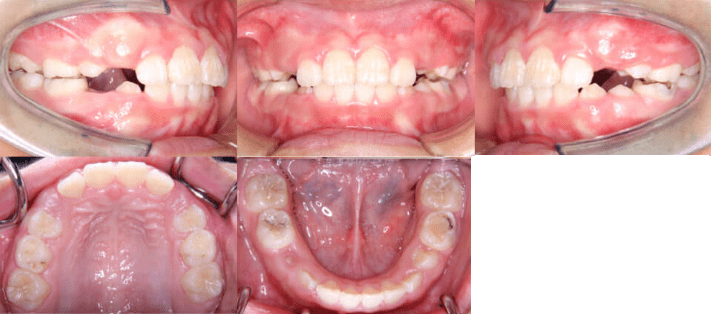

治療後

• 初診時年齢:8歳5ヶ月

• 主訴:上の前歯がでていて口が閉じづらい

• 診断:過大なオーバージェットを伴う過蓋咬合症例

• 抜歯箇所:非抜歯

• 治療内容:マウスピース型カスタムメイド矯正歯科装置(製品名インビザライン 完成物薬機法対象外)を使用して主訴である上の前歯の突出を改善しつつ、前歯のかみ合わせが深い過蓋咬合についても下の前歯を押し下げて上あごの歯ぐきを噛まなくなるように改善しました。

• 治療期間:10ヶ月

• リスク:矯正治療による歯の移動に伴う痛み、歯根吸収、虫歯

• 費用:44万円